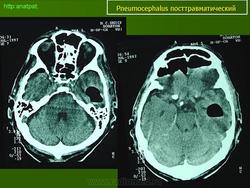

El siguiente caso corresponde a un traumatismo craneoencefálico grave, con fractura de los huesos de la base del cráneo (se observa "hemosinus" postraumático en el seno esfenoidal y en las celdillas etmoidales) y del hueso temporal izquierdo. A través de las fracturas de la base de cráneo han penetrado numerosas burbujas de aire que han difundido por el espacio subaracnoideo de las cisternas basales y de los surcos. El neumocéfalo no es muy llamativo porque se ha producido edema cerebral difuso. El parénquima encefálico ha aumentado de volumen y no ha dejado espacio libre en la cavidad intracraneal (Figuras 1, 2, 3, 4 y 5).

FIGURA 1

FIGURA 2

FIGURA 3

FIGURA 4

FIGURA 5